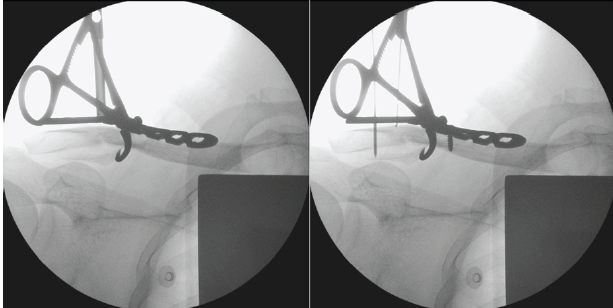

The described technique was performed on a patient who sustained a right Neer Type V distal clavicle fracture confirmed on dedicated clavicle radiographs (Fig. 1). Under general anesthesia, the patient was positioned in a beach chair at 90°. A superior approach was utilized with an incision centered over the fracture. The fracture was exposed and freshened with care to avoid excessive stripping off the surrounding soft tissues. The distal and proximal fracture fragments were reduced with the aid of bone reduction clamps. A distal clavicle 7-hole 3.5 mm locking-compression plate (Superior Clavicle Plate, DePuy Synthes, Indiana, United States) was applied and held with the aid of Kirshner wires and screws (Fig. 2).

Figure 2: Initial reduction of distal and proximal fracture fragments with bone reduction clamps and locking-compression plate.